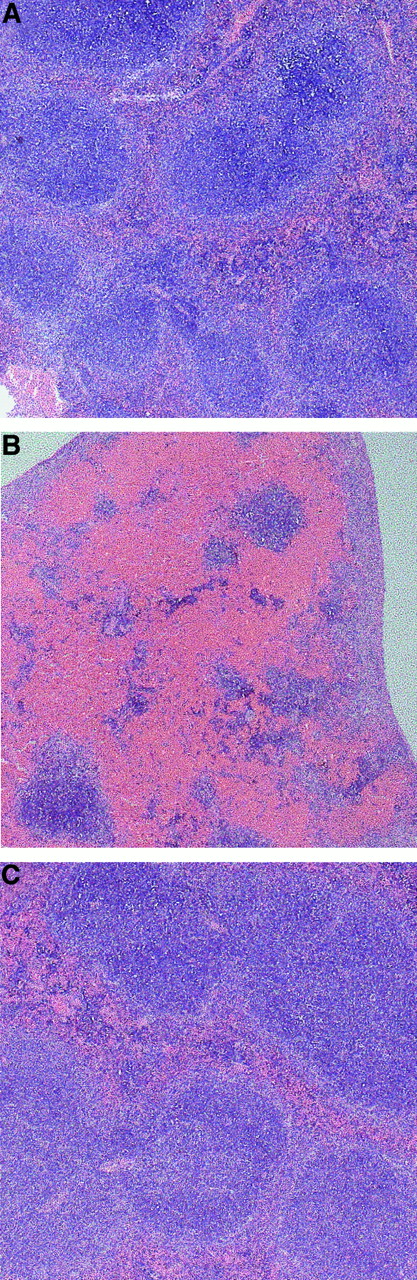

Erythrocyte accumulation in the spleen was further confirmed by light microscopic analysis of spleen sections. As shown in Figure2B, a massive accumulation of erythrocytes occurred in the red pulp of spleens from RL73 F(ab′)2-treated mice, whereas spleens from Ter119 F(ab′)2-treated mice (Figure 2C) were indistinguishable from those of unmanipulated mice (Figure 2A). Strikingly, no erythrocyte accumulation was observed in other major organs studied, such as liver, kidney, or lung from any of the mice analyzed (data not shown), suggesting selectivity of erythrocyte trapping in the spleen following CD147 blockade.

Erythrocytes accumulate in the red pulp of spleens from anti-CD147–treated mice.

DBA2 mice were injected intraperitoneally with 100 μg RL73 F(ab′)2 (B) or Ter119 F(ab′)2 (C), or left untreated (A) and killed on day 3. Spleens were removed and fixed in 10% formaldehyde. Microtome sections were then stained with hematoxylin and eosin and analyzed by light microscopy (original magnification × 25).